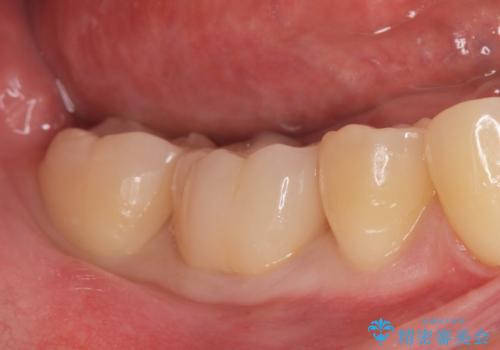

食べ物食べたら歯が欠けた。

- 過去に退院で治療した詰め物が欠けたことにより来院。

古いプラスチックの樹脂、虫歯を全て取り除き

ジルコニアクラウンにて治療しました。

- ジルコニアクラウン・仮歯 12.1万円費用は治療当時の料金となります

プラスチックの樹脂(CR)の治療は保険適応で白くて一日で

治療が終わるため安価であり、患者様の負担が少ない治療ですが

プラスチック樹脂は経年劣化して茶色くなります。

また耐久性もジルコニアクラウンに比べて低く、割れてしまうことがあります。